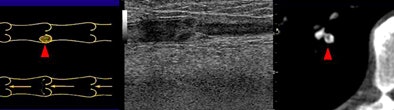

| Above, small peripheral pulmonary emboli are common and are of unknown clinical importance. Image below shows a patient with classic pulmonary embolism, with larger clots involving the central pulmonary vasculature and deep vein thrombosis. All images courtesy of Jane Suh and Dr. John Cronan. |

The retrospective study examined the medical records of 1,273 consecutive patients, of whom 101 (7.9%) were diagnosed with pulmonary embolism at CT. The researchers further evaluated 50 patients (24 men, 26 women; ages 21-90 years; mean age, 56.1 years) who also underwent lower-extremity venous ultrasound performed within seven days of the CT.

"We reviewed all images and plotted the clots on a diagram of pulmonary vasculature, and also measured the width of the most proximal clot for each patient," Suh explained.

In 32 patients (64%), extensive clotting was noted in the central pulmonary arteries (divisions 1-3), constituting classic PE, she said. In 18 of these cases (56%), deep vein thrombosis (DVT) was also diagnosed with ultrasound.

But in the 18 remaining cases diagnosed with pulmonary emboli, the researchers found only tiny clots in the fourth- through sixth-generation pulmonary arteries ranging in size from 1.5 mm to 4 mm (mean, 2.3 mm). In all, 27.7% of PE cases (28 of 101) at their institution were "dots," with an average width of 2.5 mm, she said.